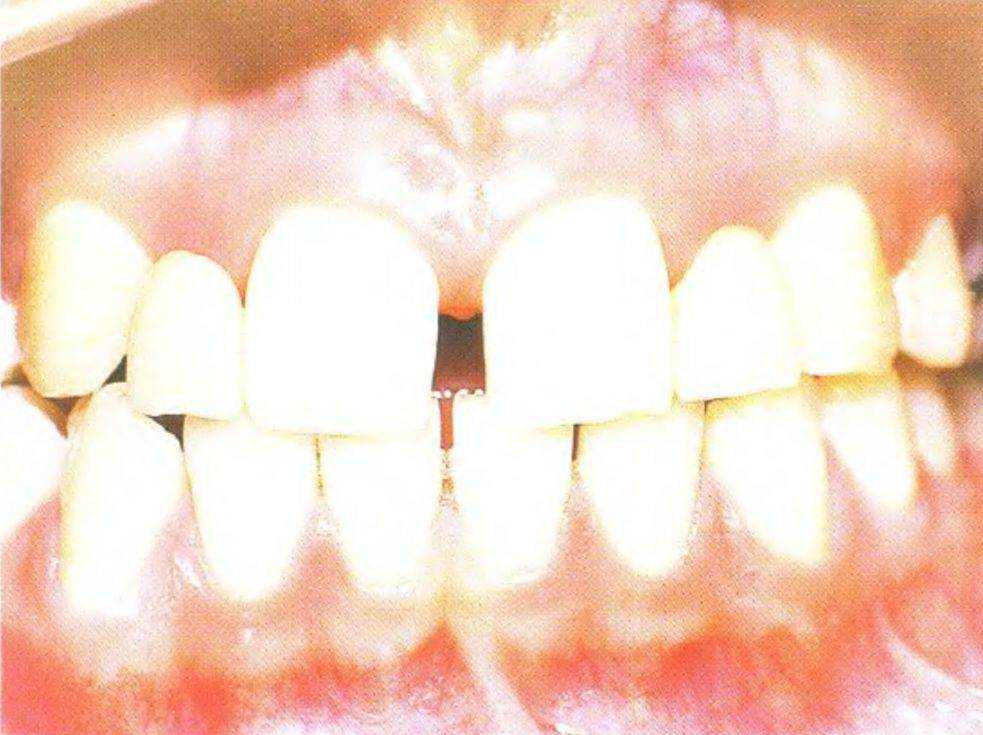

Рис. 3 39а. Пациентка 17 лет с отсутствующими латеральными резцами верхней челюсти